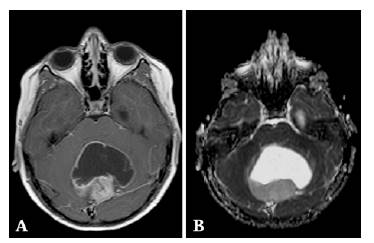

Solid mass in the midline of the posterior fossa occupying the fourth ventricle. A) post-gadolinium axial T1W-SE: the solid component exhibits avid post-contrast enhancement and peripheral diffusion restriction (not shown); B) axial ADC map: median quantitative ADC value: 0.210x10-3mm2/s. Histopathological diagnosis of medulloblastoma.

Figure 3: Solid mass in the midline of the posterior fossa occupying the fourth ventricle. A) post-gadolinium axial T1W-SE: the solid component exhibits avid post-contrast enhancement and peripheral diffusion restriction (not shown); B) axial ADC map: median quantitative ADC value: 0.210x10-3mm2/s. Histopathological diagnosis of medulloblastoma.

Source: Document obtained during the course of the study.